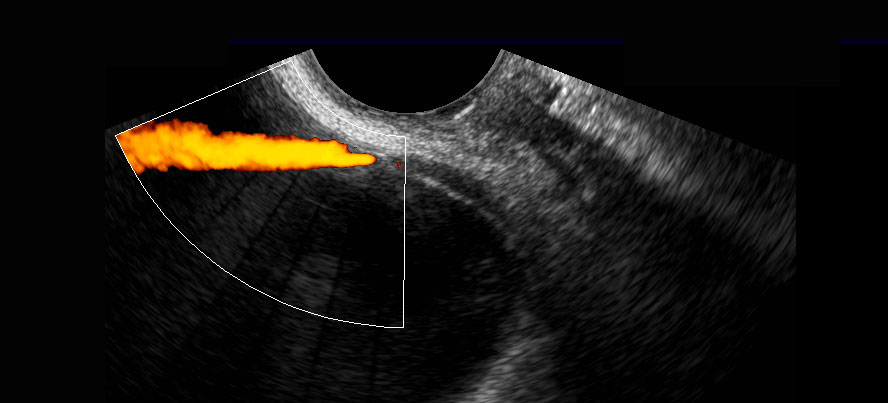

Siêu âm đầu dò âm đạo cho thấy dày thành không đều của niệu quản phải đoạn xa (đầu mũi tên). Sự kết hợp các phát hiện này làm dấy lên khả năng ác tính biểu mô đường niệu.

Bảy ngày sau, bệnh nhân hết triệu chứng mà không cần điều trị, cặn nước tiểu trở về bình thường và siêu âm đầu dò âm đạo theo dõi cho thấy niệu quản đoạn xa trở về hoàn toàn bình thường (đầu mũi tên).

Chẩn đoán cuối cùng là sỏi đi qua không được nhận biết với các biểu hiện thứ phát gây nhầm lẫn gồm dày thành niệu quản thoáng qua và các tế bào biểu mô đường niệu bất thường trong cặn nước tiểu.